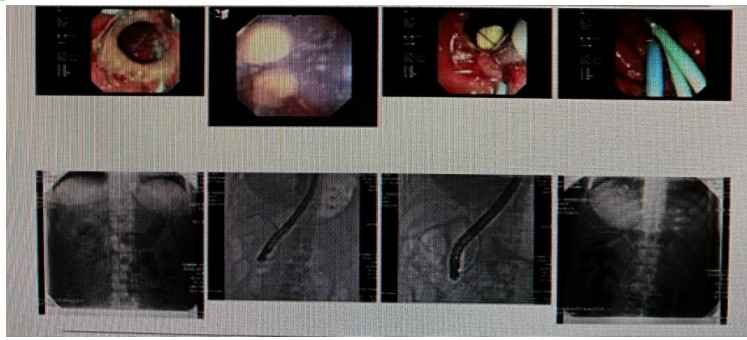

消化內(nèi)科肝病亞專(zhuān)科團(tuán)隊(duì)詳細(xì)討論,分析患者情況后,取消了周女士的肝穿刺活檢檢查,建議患者先行超聲胃鏡下膽胰掃查。在內(nèi)鏡醫(yī)師第三只眼——超聲胃鏡的掃查下,發(fā)現(xiàn)引起周女士肝功能受損的罪魁禍?zhǔn)?/span>原來(lái)是膽總管末端結(jié)石!伍友興主任醫(yī)師帶領(lǐng)團(tuán)隊(duì)給予患者行ERCP下取石后,周女士未再出現(xiàn)腹痛,肝功能恢復(fù)正常。

無(wú)獨(dú)有偶,劉先生也為反復(fù)出現(xiàn)肝功能受損到多家醫(yī)院就診檢查,未能找到原因,來(lái)到衡陽(yáng)市中心醫(yī)院消化內(nèi)科就診,希望能在肝穿刺活檢下得出病因。在行肝穿刺活檢之前,醫(yī)生建議劉先生行超聲胃鏡膽胰掃查,發(fā)現(xiàn)引起劉先生反復(fù)肝功能受損原因,亦是膽總管結(jié)石引起,在ERCP術(shù)取石術(shù)后,患者肝功能恢復(fù)正常,未再出現(xiàn)異常情況。

張丹霞主任醫(yī)師介紹,超聲內(nèi)鏡通過(guò)胃十二指腸自然腔道,可以將探頭貼近相應(yīng)的位置,近距離的觀察胰腺及膽道系統(tǒng),準(zhǔn)確捕捉到直徑小于5毫米的胰腺異常病灶及膽道系統(tǒng)病灶。而體表B超常受皮膚、脂肪或腸道氣體干擾。CT或磁共振檢查只能提供靜態(tài)圖像,且對(duì)膽胰管陰性結(jié)石或是未引起明顯膽管梗阻性的結(jié)石檢查有局限性,因此對(duì)于有輕微腹痛合并肝功能受損的患者,建議常規(guī)行超聲胃鏡下膽胰掃查。超聲胃鏡、腹部彩超、腹部CT、腹部MRI同為診斷膽管細(xì)微病變的四架馬車(chē),在膽總管結(jié)石診斷方面,超聲胃鏡膽胰掃查同ERCP一樣,是敏感性高、特異性強(qiáng)的診斷方法。超聲胃鏡發(fā)現(xiàn)可疑病變,可以完成穿刺活檢,還可行囊腫穿刺引流、膽管減壓、消融術(shù)等。